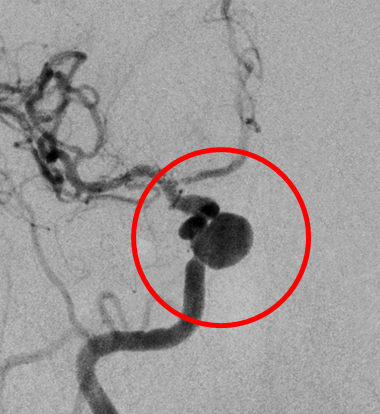

破裂内頚動脈瘤

術前の造影写真です。〇内に脳動脈瘤が造影されています。